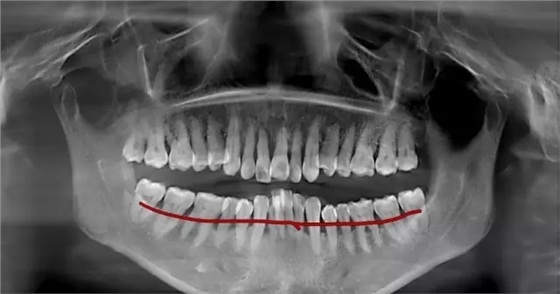

(圖中線條部位為正常牙齦位置,牙齒不光滑的表面布滿牙結(jié)石)

超聲波洗牙清潔掉牙齒表面上的菌斑和牙結(jié)石,牙齒根部的結(jié)石還未去除,且牙齦依然還會存在紅腫的情況,所以需要繼續(xù)齦下刮治治療。